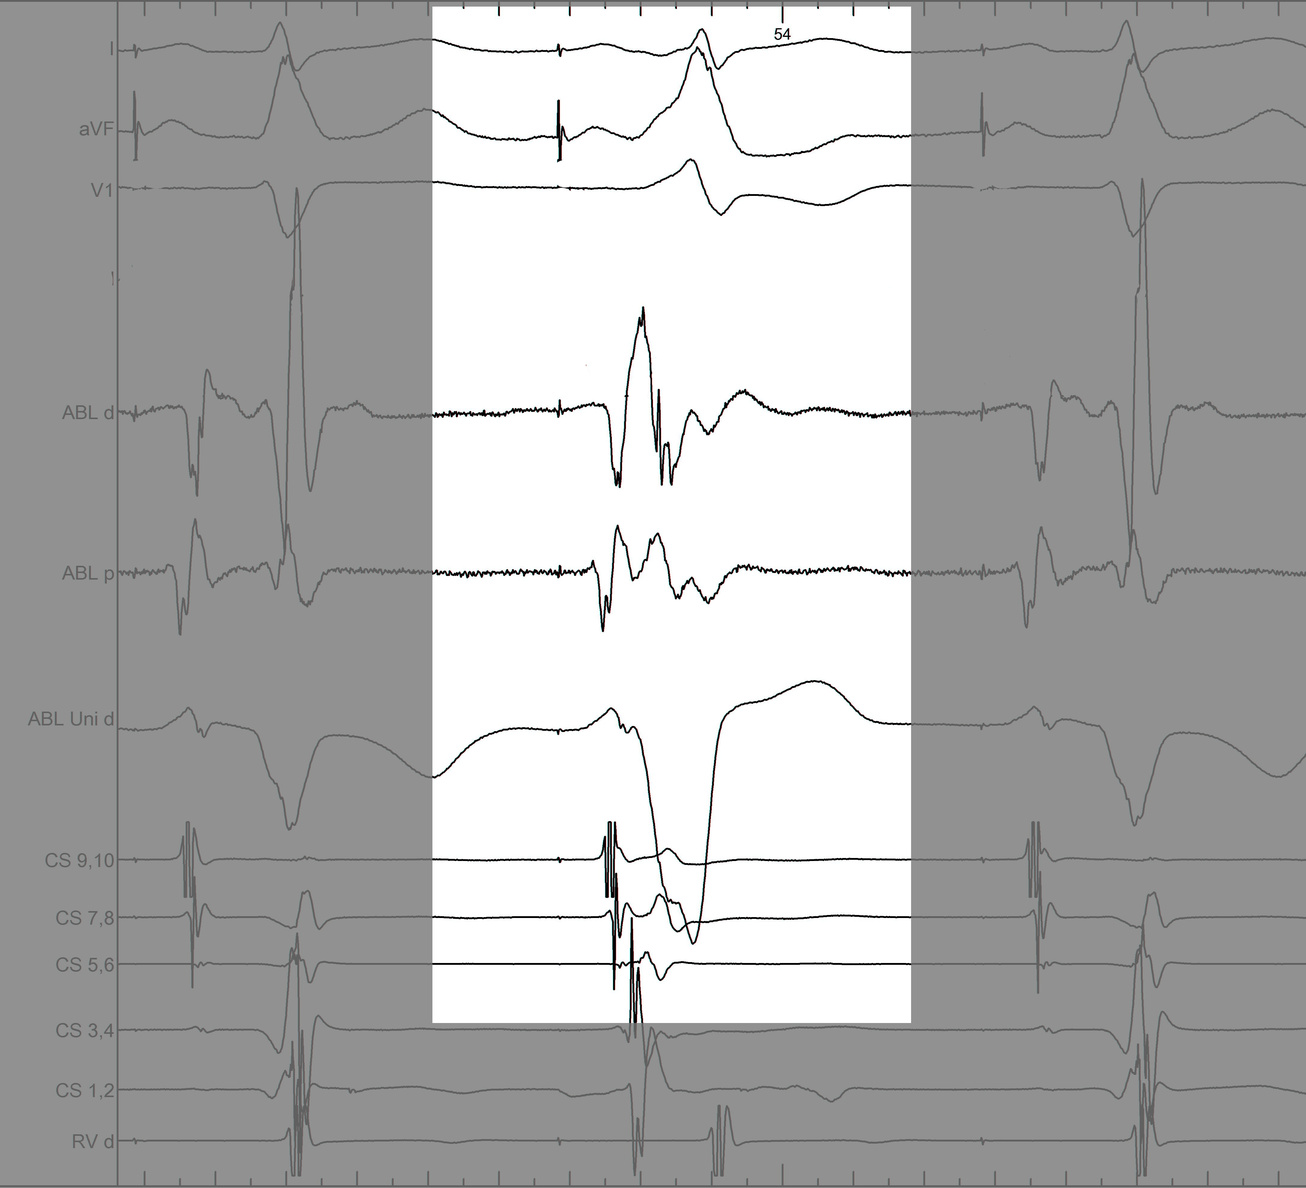

AP slant - Earliest A and earliest V may be distant

ap_med_lat1.jpg

ap_med_lat2.jpg

ap_med_lat3.jpg

AP slant - AP potential more important

pot_late_a.jpg